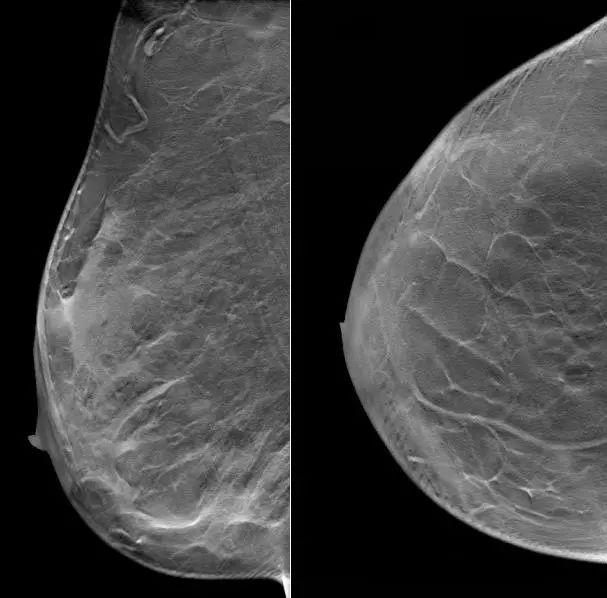

2021.6.28乳腺超声示:右乳外上象限实性肿块,考虑乳腺癌(BI-RADS-5类)。

右乳10点方向腺体层探及一实质低回声肿块,大小约35.1×22.6mm,内部回声不均匀,其内可探及多个点状强回声,边界不清,形态不规则,周边可见毛刺征,CDFI、CDE示其内血供丰富。右侧腋窝探及多个实质低回声结节,大者约10.2×5.2mm,皮质稍增宽,CDFI、CDE示其内血供不丰富。

图1. 乳腺超声

(2 cycle 后)2021.8.31 乳腺超声示:右乳10点实性肿块 44.9mm×13.1mm。

图5. 乳腺超声